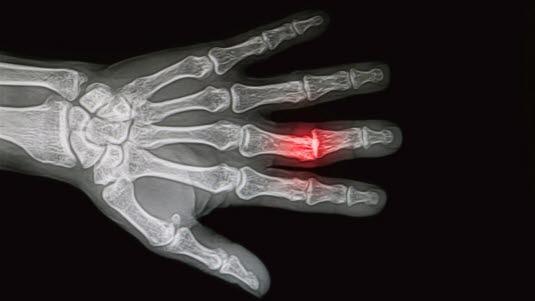

Beinbrudd og bein ut av ledd

Beinbrudd påvises eller mistenkes når man på røntgen finner tydelige eller mindre tydelige bruddlinjer. Noen ganger kan det ses som en innpressing eller utbuling av beinet. Mistanken kan også vekkes når man finner tydelig hevelse i bløtvevet rundt beinet. Noen brudd kan være vanskelig å oppdage når skaden er fersk, men de vises tydeligere når tilhelingen er startet (etter noen uker).